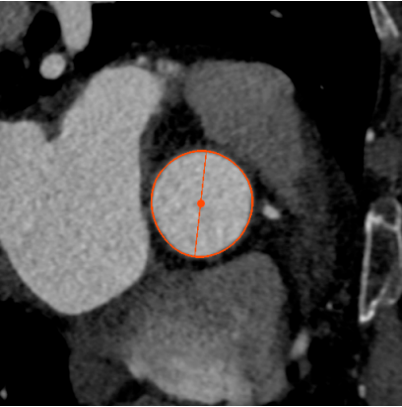

Annulus

长径: 24.8 mm

周长: 68.6 mm

面积: 352.3 mm²

LCA

下缘高度 7.1mm

上缘高度 11.9mm

瓣叶长度 11.8mm